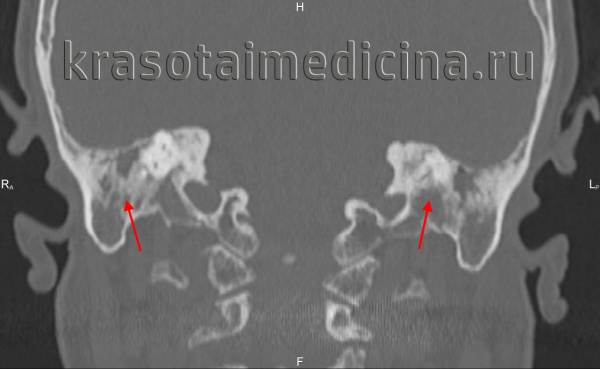

Происходящие при отосклерозе изменения костной ткани капсулы лабиринта иногда определяются по результатам прицельной рентгенографии черепа. Однако более информативным исследованием является КТ черепа, позволяющая визуализировать очаги отосклероза.

КТ височных костей. С обеих сторон диффузное снижение пневматизации ячеек сосцевидного отростка и пирамиды височной кости за счет отосклероза